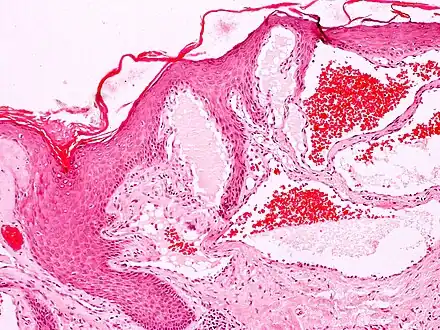

Angiokeratomas characteristically have large dilated blood vessels in the superficial dermis and hyperkeratosis (overlying the dilated vessels).

- Scrotal angiokeratoma; visible large dilated blood vessels and hyperkeratosis